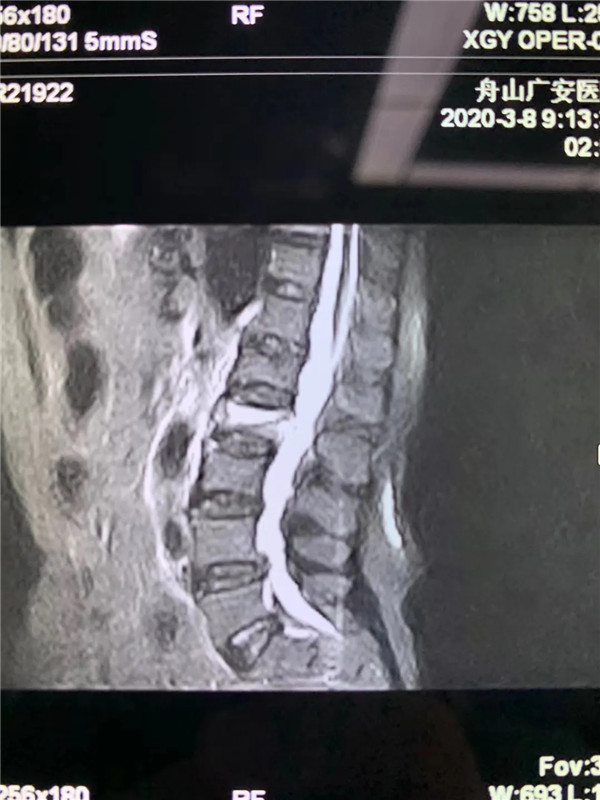

經(jīng)過仔細問診和查體后,初步診斷曹阿姨是椎體壓縮骨折了,在完善胸腰椎的MRI線檢查后,也證實了推斷。在與曹阿姨及家屬充分溝通后,戈才華主任為曹阿姨實施了微創(chuàng)手術(shù),很快為其緩解了疼痛。

(MRI顯示椎體壓縮性骨折)